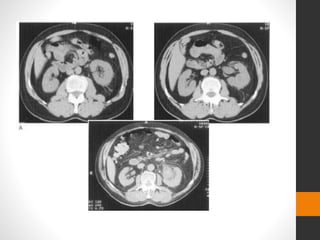

Contrast CT showing a fracture through the centre of the kidney with

considerable circumferential perinephric haemorrhage (A).

Two months after conservative management there has been impressive

healing of the kidney and resorption of most of the haemorrhage (B).